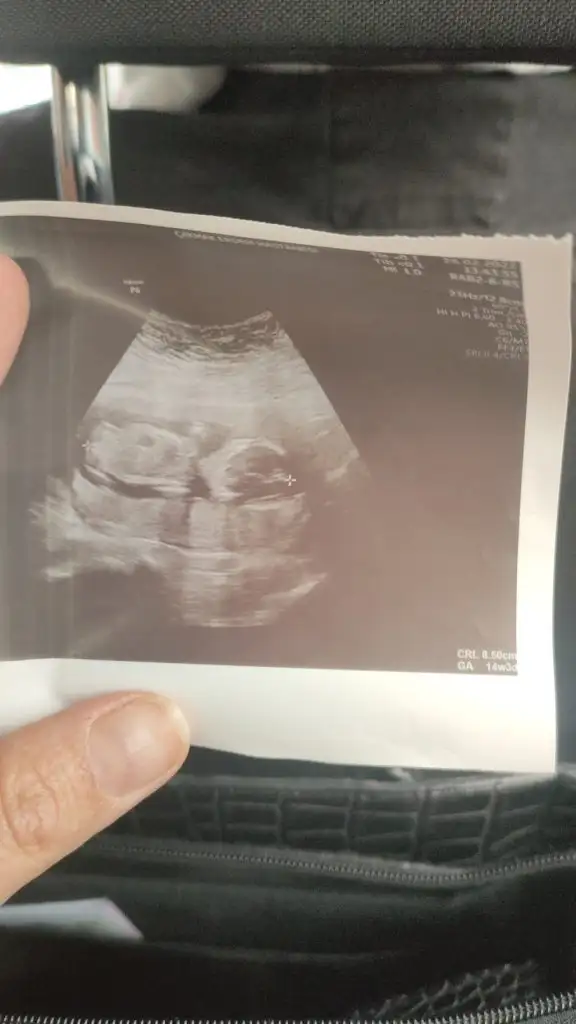

Anladım canım haftaya net söyler belkideemin olamadı kız gibi dedi sonra altta bi çıkıntı var gibi dedi. daha küçük falan dedi aklımı karıştırdı yolladı ben de sana sorayım dedim.

Kız gibi sanki

Nub olmaz büyük 11 12 13 haftalar olmalı tip kız gibi sankiEki Görüntüle 3014520 Merhaba ikra hanım bizimkine dr bişey diyemem cok erken diyor siz ne diyorsunuz 15 haftalık

@Eki Görüntüle 3014520 Merhaba ikra hanım bizimkine dr bişey diyemem cok erken diyor siz ne diyorsunuz 15 haftalık

Nub olmaz büyük 11 12 13 haftalar olmalı tip kız gibi sanki